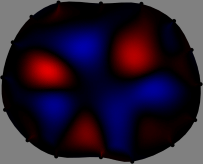

Refer to caption

Figure 2: Fidelity-embedded regularization method. (Left bottom) Correlations between four different column vectors (𝐒ksubscript𝐒𝑘{\bf S}_{k}) and all the remaining column vectors (𝐒subscript𝐒{\bf S}_{\ell}) are visualized. (Right bottom) Performances of the proposed fidelity-embedded regularization method for λ=𝜆\lambda=\infty are shown by numerical simulations.

To explain the FER method, we closely examine the correlations among column vectors of the sensitivity matrix 𝕊𝕊\mathbb{S}, described in Fig. 2. The correlation between 𝐒ksubscript𝐒𝑘{\bf S}_{k} and 𝐒subscript𝐒{\bf S}_{\ell} can be expressed as

for i=1,,16𝑖116i=1,\cdots,16[23]. This shows that the column vector 𝐒ksubscript𝐒𝑘{\bf S}_{k} is like an EEG (electroencephalography) data induced by dipole sources with directions uj,j=1,,16formulae-sequencesubscript𝑢𝑗𝑗116\nabla u_{j},j=1,\cdots,16 at locations ΔksubscriptΔ𝑘\Delta_{k}. Given that two dipole sources at distant locations produce mutually independent data, the correlation between 𝐒ksubscript𝐒𝑘\mathbf{S}_{k} and 𝐒subscript𝐒\mathbf{S}_{\ell} decreases with the distance between ΔksubscriptΔ𝑘\Delta_{k} and ΔsubscriptΔ\Delta_{\ell}. Fig. 2 shows a few images of the correlation 𝐒k,𝐒(|𝐒k||𝐒|)1subscript𝐒𝑘subscript𝐒superscriptsubscript𝐒𝑘subscript𝐒1\left\langle\mathbf{S}_{k},\mathbf{S}_{\ell}\right\rangle(|\mathbf{S}_{k}||\mathbf{S}_{\ell}|)^{-1} as a function of \ell for four different positions ΔksubscriptΔ𝑘\Delta_{k}. The correlation decreases rapidly as the distance increases. In the green regions where the correlation is almost zero, 𝐒subscript𝐒{\bf S}_{\ell} is nearly orthogonal to 𝐒ksubscript𝐒𝑘{\bf S}_{k}.